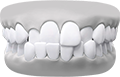

Overbite teeth illustration – upper teeth overlap lower

ฟันหน้ายื่น (ฟันสบลึก)

แก้ไขฟันสบลึก เพื่อรอยยิ้มที่สมดุล

ฟันสบลึกเกิดขึ้นเมื่อฟันบนยื่นทับฟันล่างมากเกินไป หากปล่อยไว้โดยไม่รักษา อาจส่งผลต่อรูปลักษณ์และสุขภาพช่องปาก การรักษาทางทันตกรรมจัดฟันมีเป้าหมายเพื่อฟื้นฟูความสมดุลและการทำงานของฟัน เพื่อให้คุณมีรอยยิ้มที่มั่นใจ

Underbite teeth illustration – lower teeth in front

ฟันล่างยื่น (รีเวอร์ส โอเวอร์เจ็ต)

การแก้ไขฟันสบล่าง เพื่อความมั่นใจและการใช้งานที่มีประสิทธิภาพ

ฟันสบล่างคือภาวะที่ฟันล่างยื่นออกมามากกว่าฟันบน ซึ่งมักส่งผลต่อการเคี้ยวอาหารและความสมดุลของใบหน้า การจัดฟันสามารถช่วยปรับแนวขากรรไกรให้ถูกต้อง ช่วยเพิ่มทั้งประสิทธิภาพในการใช้งานและความสวยงามของใบหน้า

Teeth gap or spacing malocclusion diagram

ช่องว่างระหว่างฟัน (Diastema)

Crossbite teeth model – misalignment of dental arches

การสบฟันแบบไขว้ (Scissor Bite)

Crowded teeth model – overlapping or twisted teeth

ฟันซ้อน (Overcrowded Teeth)

Open bite model – space between upper and lower teeth

การสบฟันแบบเปิด (Anterior Open Bite)